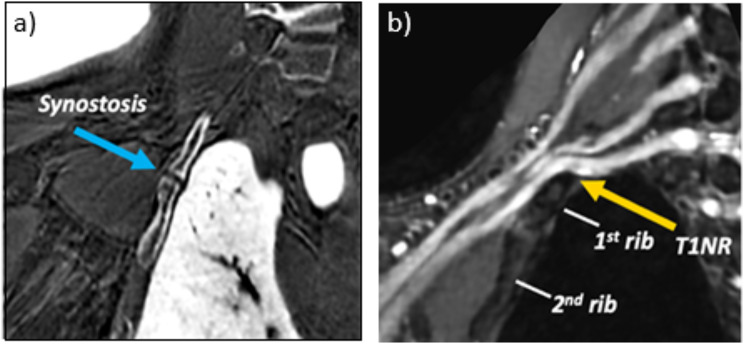

Methods: A 28-year-old man presented with chronic right upper limb discomfort and paresthesias extending from the shoulder region to the third and fourth digits. The subject underwent evaluation with a unilateral brachial plexus MR neurography protocol at 3.0 Tesla for suspicion of TOS. The protocol included T2-weighted, 3D fast spin echo short-tau inversion recovery (STIR-FSE) and 3D radial ZTE sequences for depiction of the nerves and bones, respectively. The first rib and its synostosis impinged upon the inferior aspect of the T1 nerve root (T1NR), with accompanying mild enlargement of the T1NR. A 3D printed anatomic model was created and included: (1) bone (spine, ribs, clavicle, scapula, and humerus), (2) brachial plexus, and (3) costal cartilage.

Results: The 3D printed model clearly demonstrated a T1NR impingement from the synostosis, confirming the diagnosis of neurologic thoracic outlet syndrome (TOS) and guided the treatment approach in prescribing TOS-specific physical therapy, which led to significant improvements in the patient's condition.